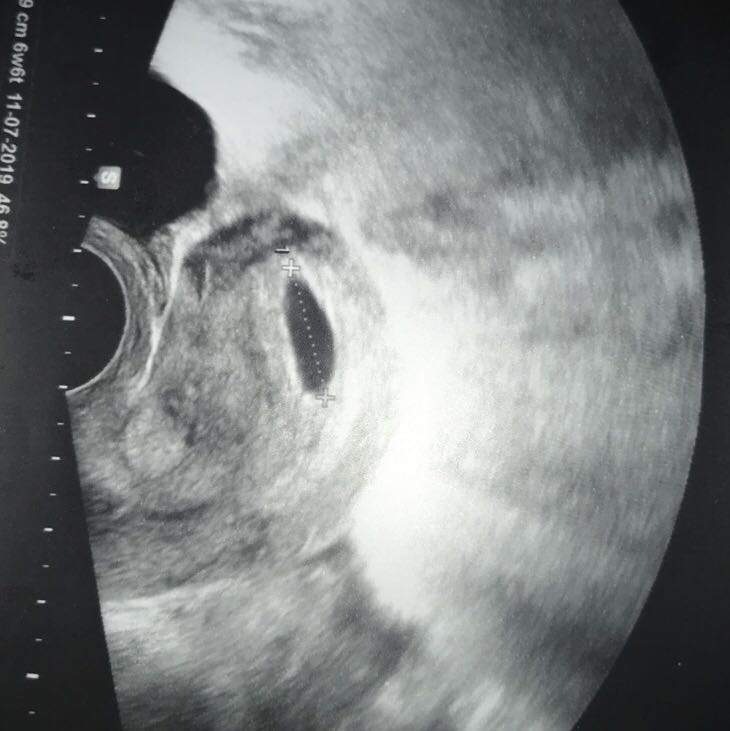

Ssw 7 2 ultraschall. 75 SSW der 7. Geschmacksveränderungen Heisshunger und Übelkeit. Juli 2014 um 1026 Hey ich war gestern beim Arzt und habe mir nach einen Positiven Schwangerschaftstest meine Schwangerschaft bestätigen lassen.

Leere Fruchthöhle 72 SSW. Juli 2014 um 913 Letzte Antwort. Größe und Entwicklung des Embryos.

Das ist zu sehen. Wie wird die 7. War ich beim ersten Ultraschall da hat man nur die Fruchthöhle und einen Dottersack.

SSW oft einen seltsamen Geschmack im Mund haben. Das heißt wenn du etwas über diesen Link kaufst bekommen wir eine kleine Provision. Ab Ende dieser Woche ist sogar der Herzschlag beim Ultraschall zu erkennen und Herz und Kopf sind getrennt voneinander darstellbar.

Sprichwörtlich für eine frühe Schwangerschaft ist derganz plötzlich auftretende. Schwangerschaftswoche 70 bis 76 ist Ihr Baby 15 g schwer und 9 mm groß SSL -. Schwangerschaftwoche 62 SSW. War ich beim ersten Ultraschall da hat man nur die Fruchthöhle und einen Dottersack. Es misst bereits 6-7 mm Scheitel-Steiß-Länge. Dieses Bild ist ähnlich wie das obige und zeigt ebenfalls einen 4 Millimeter großen Embryo. 7 SSW ausgerechnet mit dem arzt aber beim Ultraschall 6 SSW festgestellt. Das Babys misst etwa 6mm Alles über den Mutterpass Papa und die Schwangerschaftshormone. Das heißt wenn du etwas über diesen Link kaufst bekommen wir eine kleine Provision.

Du kannst dir also aussuchen ob du ihn zu Beginn z. Dabei startet die Berechnung etwa zwei Wochen vor der Befruchtung. Leere Fruchthöhle 72 SSW. Das Baby ist inzwischen bereits 5 Wochen in deinem Bauch und nimmt immer mehr die Formen eines kleinen Menschen an. Dieses Bild ist ähnlich wie das obige und zeigt ebenfalls einen 4 Millimeter großen Embryo. Schwangerschaftswoche 70 bis 76 ist Ihr Baby 15 g schwer und 9 mm groß SSL -. Das Babys misst etwa 6mm Alles über den Mutterpass Papa und die Schwangerschaftshormone.